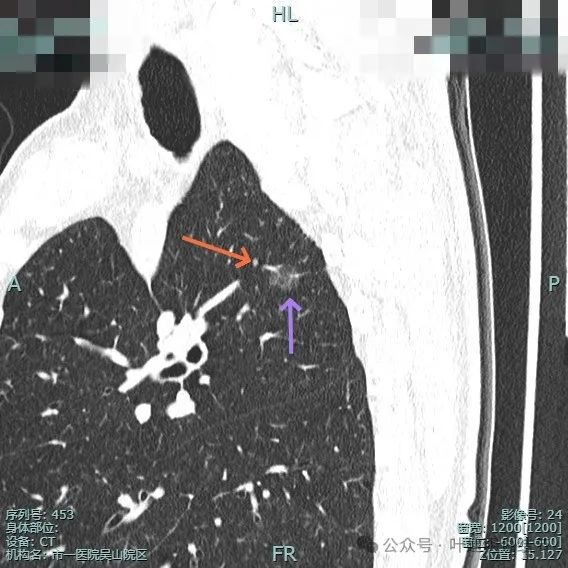

病灶6:右上叶后段磨玻璃结节,有浅分叶征,结合前面图上有血管穿行,考虑是肿瘤范畴的,以微浸润性腺癌或浸润性腺癌贴壁为主型可能性大。

血管穿行明显,表面有毛刺征,灶内有空泡征。

分叶明显,灶内点状高密度(血管穿行)表面有细小毛刺征。

灶内密度略显不均,有空泡征,表面有毛刺征。

毛刺与血管进入,整体是纯磨,轮廓与边界清。

少许毛刺,整体轮廓清。

血管穿行并发现细小分支的样子,表面不平有细毛刺,灶内有小空泡征。

血管穿行并略有增粗,表面不平有浅分叶,整体轮廓与边界清。

血管进入并有发出分支,边缘有细毛刺,表面不光滑,整体轮廓清,瘤肺边界清楚。